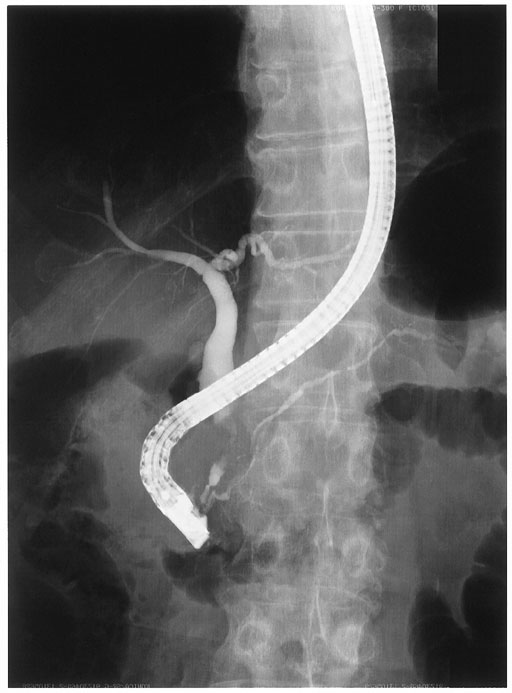

図2:

膵頭部に限局性狭窄像を認める.